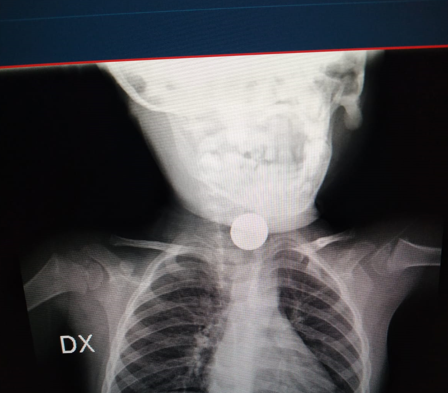

Arrivato al presidio del Vomero vengono effettuati nuovi controlli e, da un attento esame radiografico, si capisce che il corpo estraneo fermatosi in esofago è una disk battery che, ormai, è tenacemente aderente all’esofago con una progressiva necrosi dei tessuti.